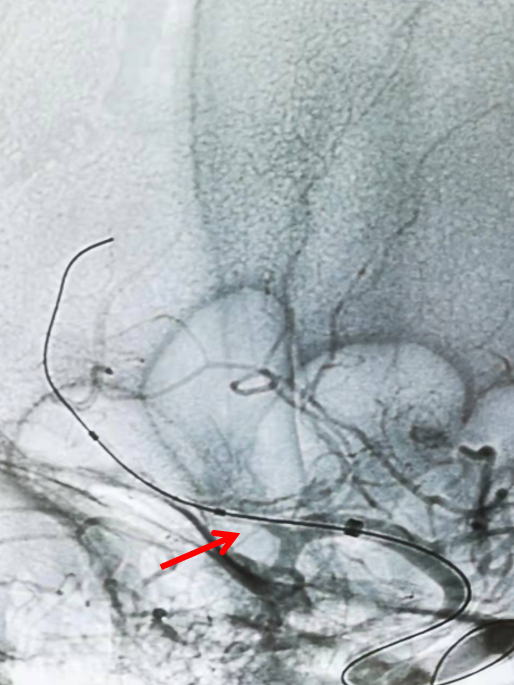

headway17微导管在3m的Synchro-14导丝辅助下,谨慎通过闭塞处,撤出微导丝,微导管造影证实在真腔(左图),而后将微导丝置于闭塞血管远端后撤出微导管(右图)。

Headway17微导管在3m的Synchro-14导丝辅助下,谨慎通过闭塞处(左图箭头示),撤出微导丝,微导管造影证实在在闭塞远端血管真腔(右图箭头示)。

通过微导管给予路径图,而后将微导丝置于闭塞血管远端后撤出微导管(图箭头示)。